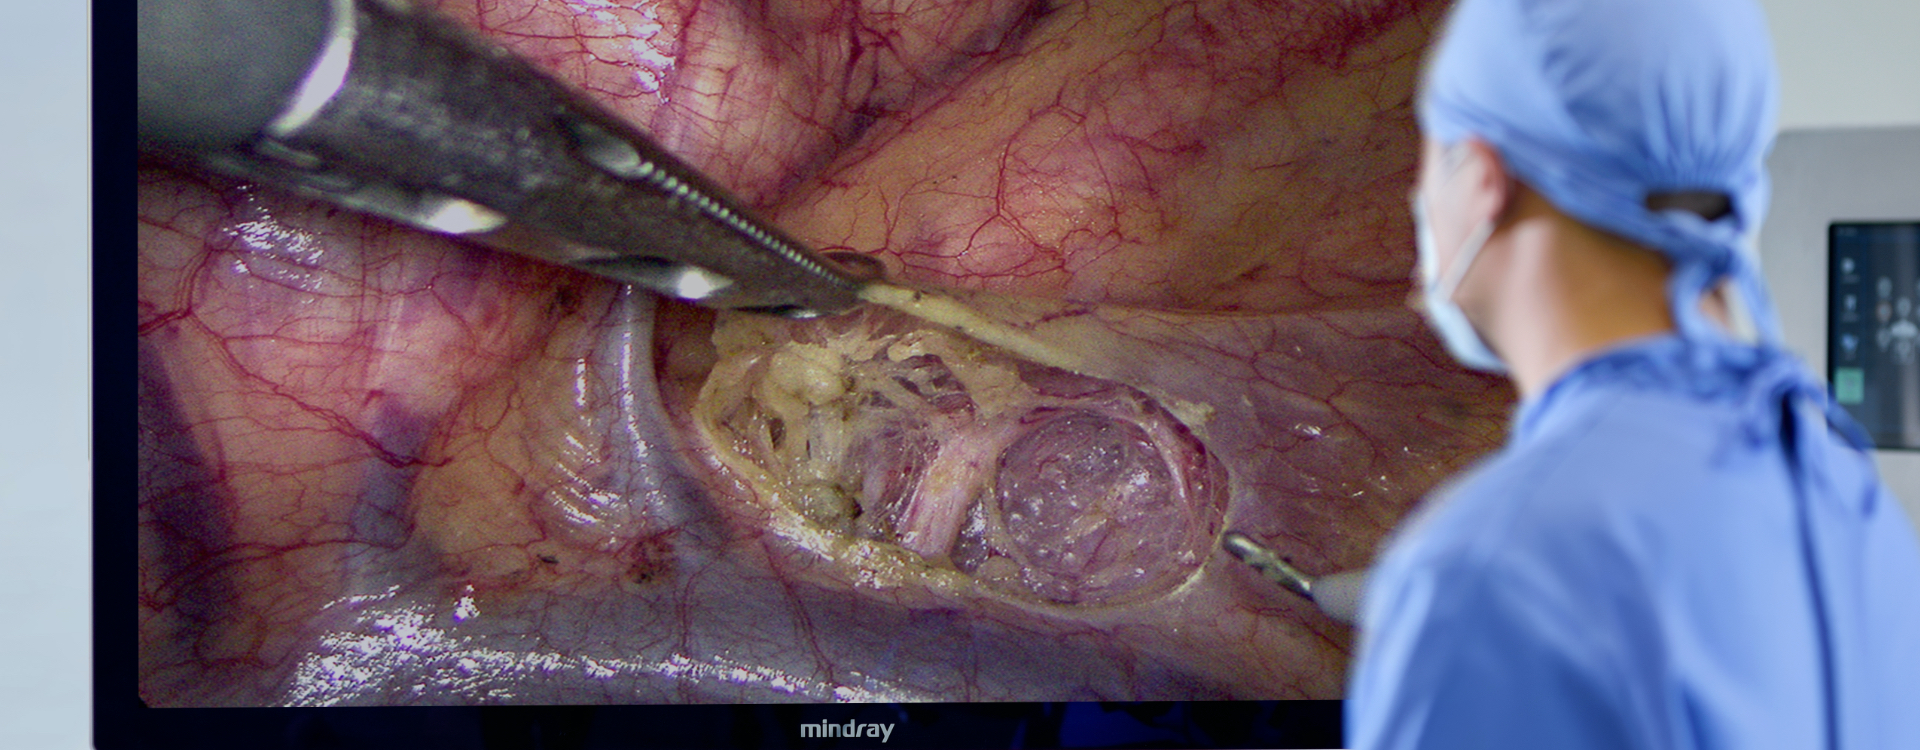

Resoluci├│n 4K

Obtenga una imagen de ultra alta definici├│n con una resoluci├│n de 3840├Ś2160.

Gama de colores extendida

Restaura los ├│rganos y tejidos en color real; perfecta identificaci├│n de vasos sangu├Łneos, ganglios linf├Īticos y nervios.

Profundidad de campo de 3-200 mm

El enfoque permanece n├Łtido mientras se cambia entre varias escenas operativas.

Experiencia envolvente de 55 pulgadas

La imagen quir├║rgica se ampl├Ła sin reducir la resoluci├│n, por lo que los detalles ya no son peque?os y se reduce la fatiga visual del m├®dico.